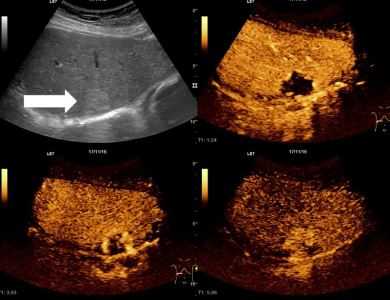

При проведении УЗИ печени могут определяться очень плотные участки (кальцификаты) и полости, заполненные жидкостью (кисты, абсцессы). Злокачественные неоплазии органа на УЗИ печени выглядят как участки необычного строения с неравномерной эхогенностью, неоднородной структурой и нечеткими границами. Плотность метастазов может быть как выше, так и ниже плотности ткани печени (в зависимости от плотности первичного новообразования), характерным признаком данной патологии является гипоэхогенный ободок вокруг патологического очага. Гемангиома при УЗИ печени представляет собой гиперэхогенное образование с четкими границами и акустической дорожкой, располагающееся рядом с крупными сосудами.

По данным УЗИ печени в остром периоде гепатита определяются увеличение размеров и плотности органа в сочетании с неоднородностью структуры паренхимы. При хроническом гепатите на УЗИ печени выявляются увеличение органа, неоднородность паренхимы и неясность сосудистого рисунка. При циррозе наблюдаются мозаичность и бугристость структуры, закругленность краев и расширение углов органа. При жировом гепатозе обнаруживается повышение эхогенности (светлая печень). Все перечисленные заболевания диагностируют по результатам комплексного обследования, которое, наряду с УЗИ печени, может включать в себя лабораторные исследования, КТ, МРТ и другие диагностические методики.